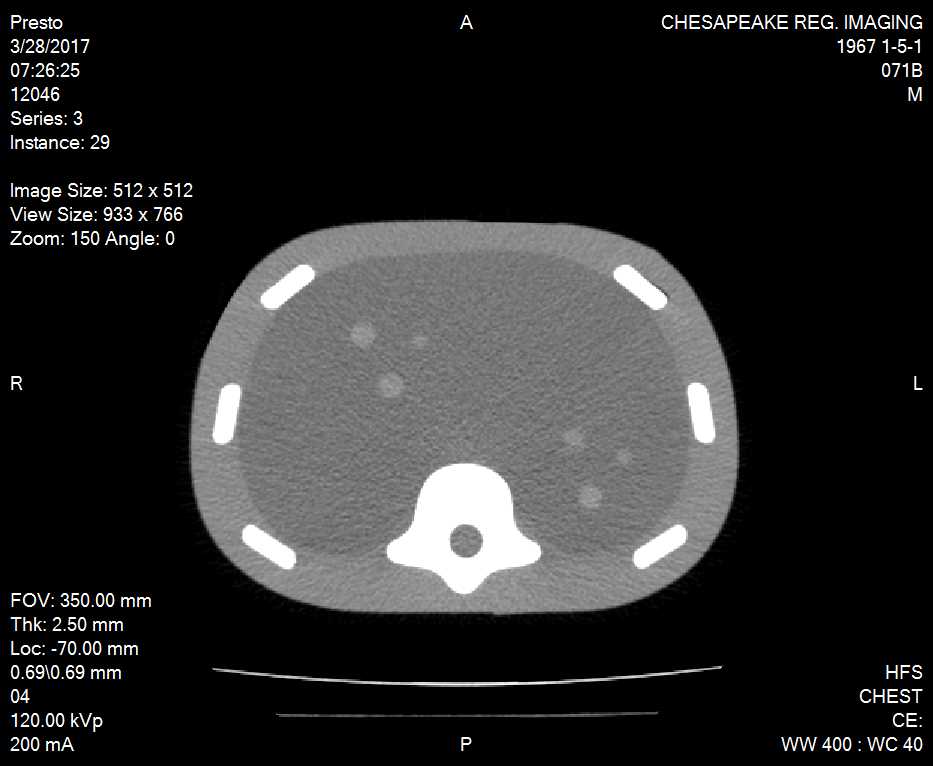

The Image-Guided Abdominal Biopsy Phantom is a simplified abdominal phantom. It’s suitable for training and demonstrating image-guided needle biopsy navigation tools or procedures that require a constant visual reference for needle placement. The phantom allows many uses over time because of the background gel minimizes needle tracks when punctured.

The phantom contains 12 lesions, 5-12 mm in diameter, positioned in groups of three in consistent locations within the phantom. It also includes simulated spine and ribs, and an “H” marker within the spine to assist in determining the head side within a CT-image. You can see the lesions and spine under ultrasound, CT and MRI. The solid polymer gel background is anechoic and will also not leak when it is punctured.

The phantom also includes a foam lined hard carry case and it’s useful in multiple fields. The phantom is perfect for CT, Ultrasound and MRI, live scanning and biopsy training.